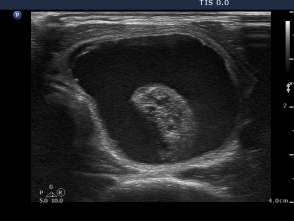

Three month prior to sclerotherapy (1st row of images)

Clinical presentation: a 50-year-old woman noticed a lump in the neck for 3 months. Thesize of the lesion did not changed over time.

Palpation: a firm nodule in the left lobe. The lesion was painless.

Functional state: euthyroidism with TSH 1.08 mIU/L.

Ultrasonography: the thyroids were echonormal. A large central-type cyst occupied almost the entire left lobe.

We tried to remove the cystic fluid but only 1.5 ml brown gelatinous fluid could be aspirated. Aspiration cytology resulted in benign cystic lesion.

We suggested a repeat aspiration 3 months later.